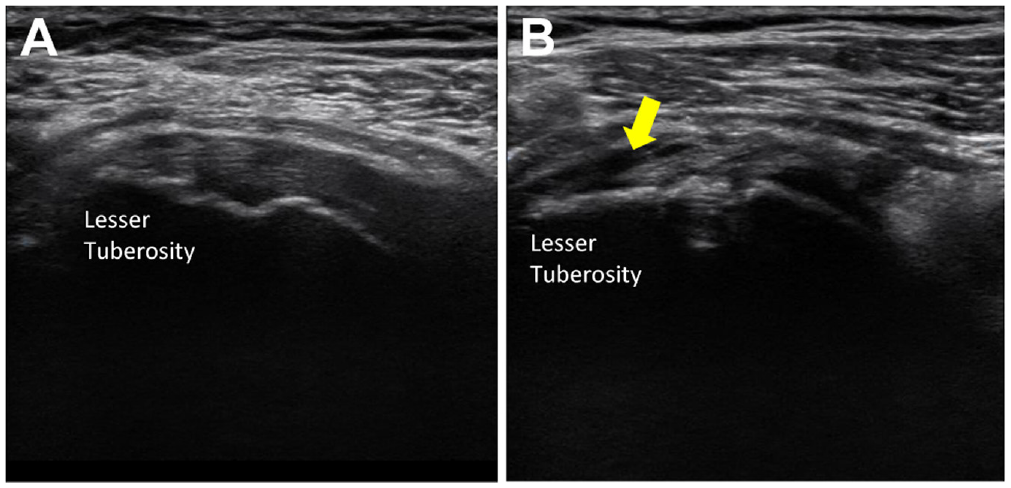

Of the 77 study patients, 40 underwent ultrasound assessment at the final follow-up. Within these patients, 35 (87.5%) repairs were classified as healed, and 5 (12.5%) were classified as unhealed (Figure 2). PROs improved significantly from pre- to postoperative periods in both groups (

Postoperative images of the SSC tendon with arthroscopic repair. (A) The healed state of the SSC with tendon continuity up to its footprint (lesser tuberosity). (B) The unhealed (retear) state of the SSC, with a monitored hypoechoic field in the lesser tuberosity. The arrow indicates the tear location. SSC, subscapularis.